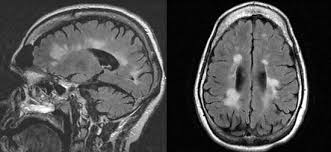

Multiple sclerosis (ms) is a chronic inflammatory, demyelinating, and neurodegenerative disorder of the central nervous system (cns) that affects the white and grey matter of the brain, spinal cord, and.

Multiple sclerosis (abbreviated ms, known as disseminated sclerosis or encephalomyelitis disseminata) is an inflammatory disease in which the fatty myelin sheaths around the axons of the. Multiple sclerosis (ms) is a chronic autoimmune debilitating disease in which nerve damage (demyelination of neurons) in the brain and spinal cord disrupts their communication with the body. Multiple sclerosis information including symptoms, diagnosis, treatment, causes, videos, forums, and local community support. Find answers to health issues you can trust from healthgrades.com. Ms causes gradual destruction of myelin (demyelination) and breakdown of neuronal axons throughout the brain and spinal cord.

Ms causes gradual destruction of myelin (demyelination) and breakdown of neuronal axons throughout the brain and spinal cord. Find answers to health issues you can trust from healthgrades.com. Multiple sclerosis (ms) symptoms, causes, treatment, life expectancy. Multiple sclerosis (ms) is a chronic inflammatory disease in which the myelin sheath on the nerve endings gets inflamed and damaged. Read current research articles and learn about multiple sclerosis diagnosis, symptoms as well as the latest ms treatment options. In ms , the immune system attacks the protective sheath (myelin) that covers nerve fibers. Multiple sclerosis (ms) is an autoimmune disease in which the body's immune system attacks its multiple sclerosis is estimated to affect 2.8 million people worldwide. Multiple sclerosis (ms) is thought to be an autoimmune disease;

It is caused by destruction of the myelin insulation covering. Multiple sclerosis (ms) is a chronic, inflammatory, noninfectious disease that affects the central nervous system (cns). Multiple sclerosis (ms) symptoms, causes, treatment, life expectancy. This leads to scarring of the neurological tissue in the brain and. Information from the national library of medicine's medlineplus multiple sclerosis. Multiple sclerosis (ms) is an unpredictable disease of the central nervous system that disrupts the flow of information within the brain, and between the brain and body. Primary progressive multiple sclerosis (ppms). Multiple sclerosis (ms) is thought to be an autoimmune disease;